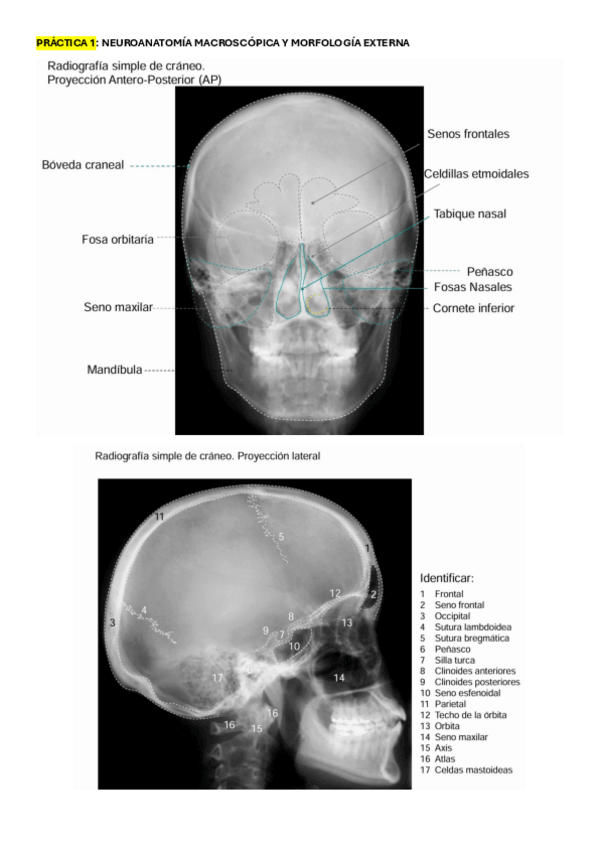

He publicado nuevos practicas de 4º neuroanatomía y anatomía de los órganos de los sentidos: todo-PRACTICAS-NEUROANATO.pdf

47 páginas